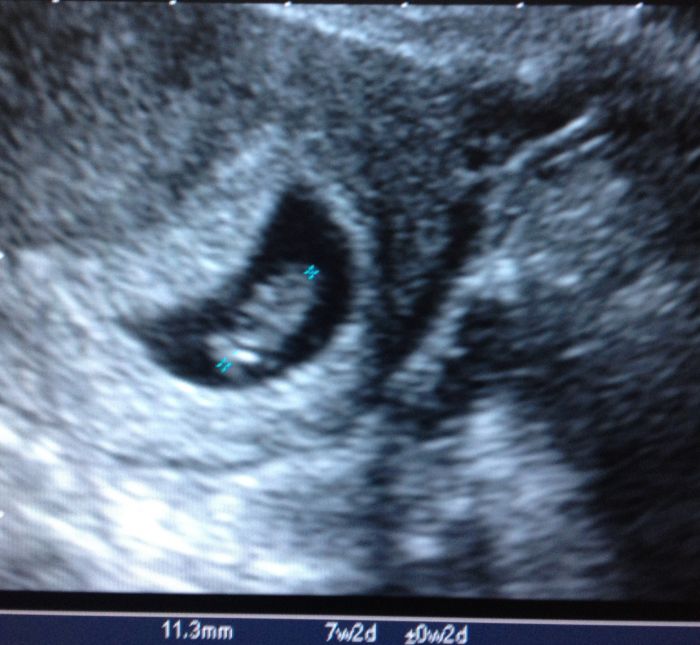

Ahoj holky a mimca, no my uz máme jednoho kloucka a další na ceste a stále je to přítel. Chci si svatbu užít či opít. No to je jedno, proste nechci aby se pak říkala musel si ji vzít. A popravdě kdyz se občas neshodnem, tak jsem pevne rozhodnuta, ze si ho nevemu :} o ruku me požádal 11.11.11 i s prstynkem. Pak 12.12.12 bez prstynku. A ted jsem zvědavá co bude dal :) :) :) holky tak ja vám vložím foto mého prvního ditka. Aby jste viděli jakou krasnou fotku jsem měla od svého Dr. a pak k porovnání i tu z pondělka. Fakt mega rozdíl. Jinak po 2 letech jsem se vyspala! Jen vím ze jsme lehla a pak probudila oči a říkám si to je světla. Maly spí a ze ja jsem k nemu v noci vstavat nemusela? :) no a hned zacal kmitat nozkama a křičet se zavřenýma očima hlady, ale az v 6 :))))